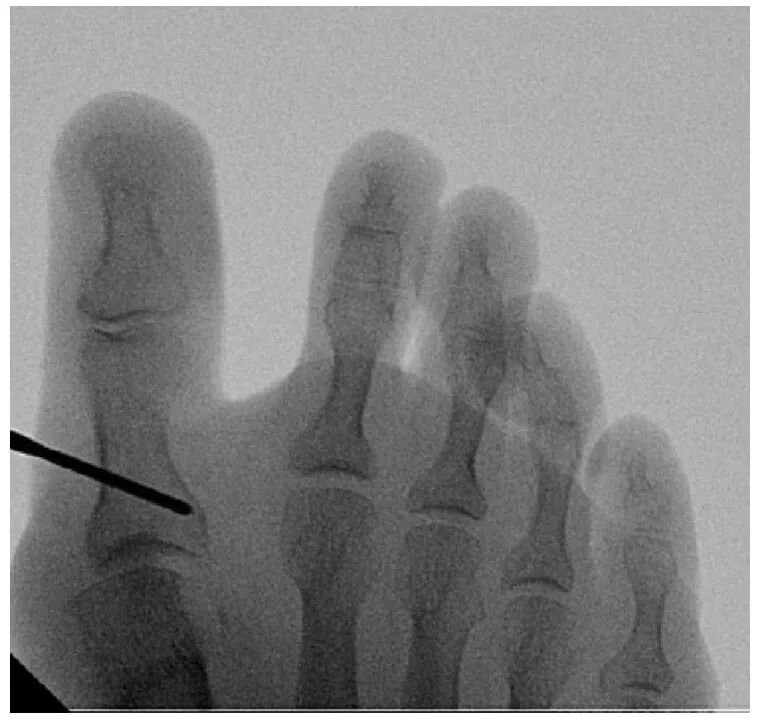

在拇囊炎近端做一个3毫米的切口。随后引入经皮骨锉,将第一跖趾关节囊与内侧、背侧和外侧的骨分离。使用1毫升生理盐水扩张第一跖趾关节囊。使用2.9×15毫米钻头进行有限的拇囊炎切除术。持续冲洗用于冷却钻头和骨骼,并使用骨锉去除关节内骨碎片。通过透视控制确认拇囊炎切除术效果。远端软组织松解包括部分关节囊切开术和内收拇肌肌腱切断术,通过第一跖趾关节外侧的3毫米切口进行。

通过同一个内侧切口,引入2.0×19.5毫米钻头(进行第一跖骨截骨术。截骨术包括3个不同的截骨面:背侧、内侧和外侧。使用Sawbone模型来说明进行三平面截骨术所涉及的不同截骨及其方向。背侧截骨的深度为第一跖骨高度的1/3。内侧截骨从远端向近端开始,与跖骨长轴成45度角。再次通过内侧切口插入钻头进行外侧截骨,此时与跖骨长轴成30度角。内侧截骨比外侧截骨更短、更陡峭,以促进远端骨块的可控侧向平移。这种几何设计倾向于将位移限制在单一方向,提高矫正的可预测性。为避免头部抬高,钻头在冠状面朝向约10度的跖侧方向。

截骨完成后,将弯曲的骨膜剥离器插入截骨部位,以平移第一跖骨头。通过近节趾骨基部内侧的3毫米切口进行额外的Akin截骨术。使用一枚2毫米克氏针通过截骨端沿拇趾内侧软组织向远端穿过,从趾尖的跖内侧穿出。然后将克氏针逆行插入第一跖骨的髓管。